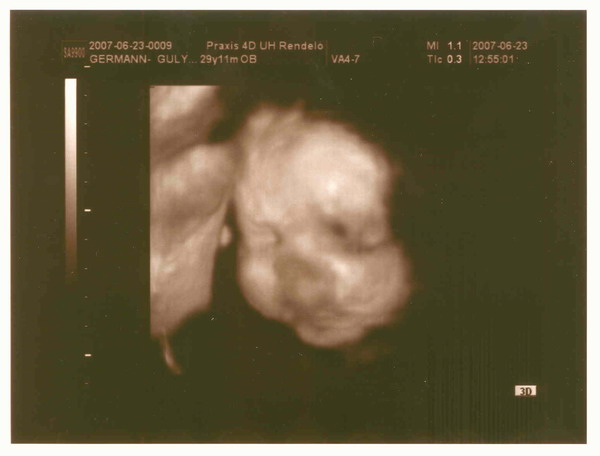

Nektarin, múlnak már a sebek a karodon? Szép kismama vagy, nagyon jók az uh. képek, nagy élmény volt így látni igaz? Én is élveztem anno. Jó pocakosodást, már nincs is sok hátra.